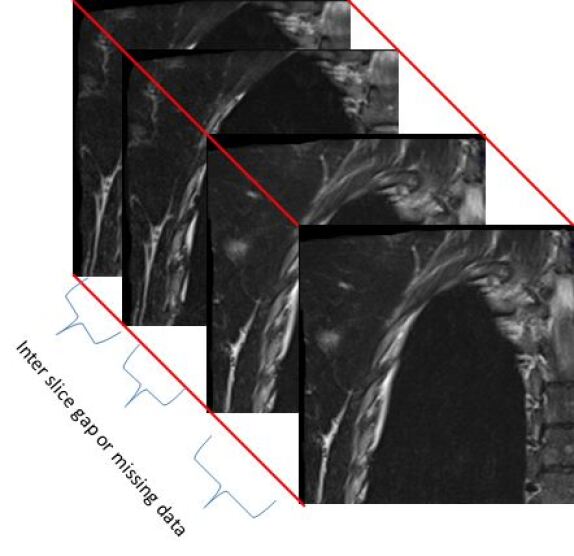

Figure 3: Sequence of original 3D sub-images with missing data for a human spine

Initially, the 2D2𝐷2D slices are split in 4 sub parts as shown in Figure 2 for a human spine, and the data set in divided in two parts. We use single instruction multiple data architecture using 8 logical cores. In parallel, for each block of sub-image, a 3D3𝐷3D matrix is created which is filled with the corresponding data leaving the specified slice gap in between slices as specified for each set as shown in Figure 3. Then edge preserved kriging interpolation is used to generate the 3d subimages. If we want to visualize these sub-images, then we can apply marching cube with color map and visualize the images as shown in Figure 4 and the complete 3D image for visualisation of full spine is as in Figure 5.